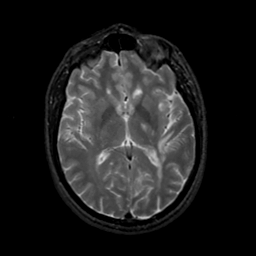

MR Study #22, December 1, 1991 -- Slice #26